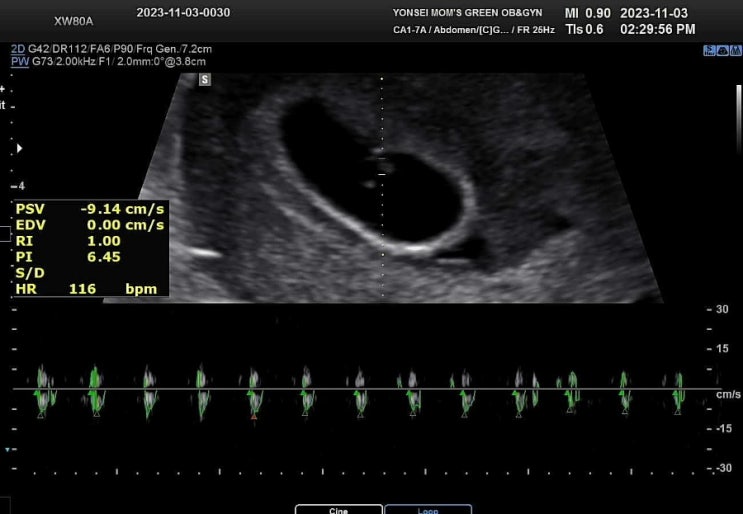

[5주 4일] 심장이바운스바운스두근대

23.11.03 / 5주 4일 크기 0.1CM 심장소리가 들린다. 1미리 세포의 심장이 뛴다. 두긍두긍두긍두긍 과학의...